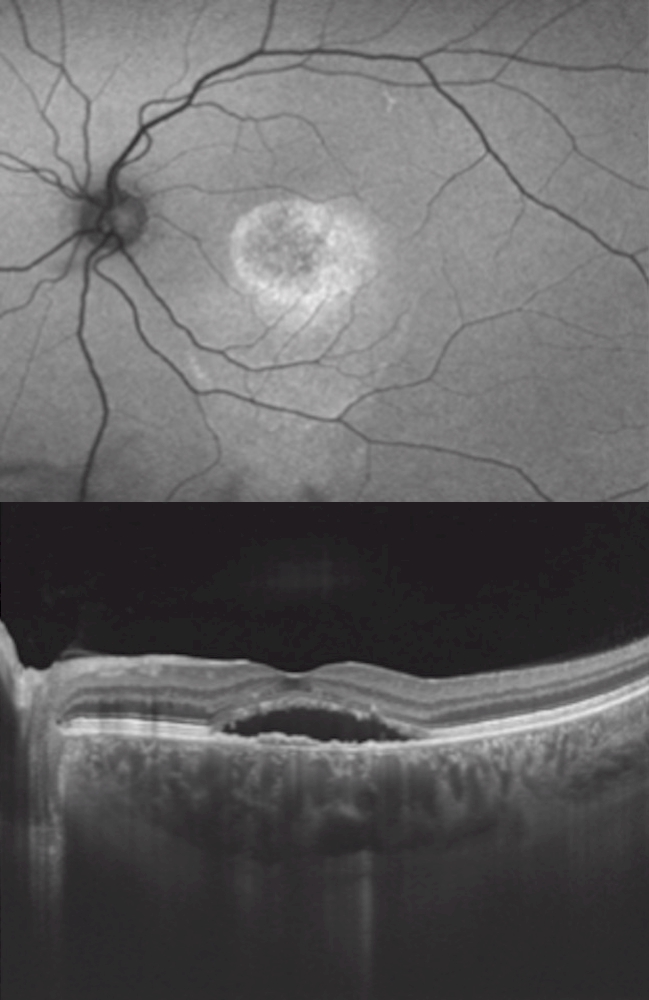

DR. GABRIEL COSTA ANDRADE

CSC - Autofluorescência e OCT